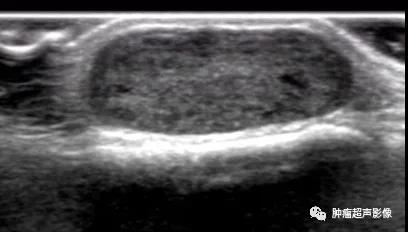

病理证实的血管平滑肌瘤,下肢、单发、可移动的疼痛结节,超声表现为皮下边界清的椭圆形低回声肿块(内见无回声),包膜完整,血流丰富,符合典型血管平滑肌瘤。